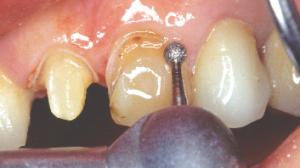

Un premier fil rétracteur fin est inséré. Il écarte légèrement la gencive.

Nous descendons la limite cervicale jusqu’à " effleurer " le fil sans toucher la gencive avec la fraise.

A aucun moment de la préparation la fraise ne doit toucher la gencive !

Les limites de préparation sont actuellement juxta-gingivales.

Un deuxième fil rétracteur plus gros est inséré au dessus du premier. La gencive est de nouveau repoussée par ce deuxième fil.

La limite cervicale est encore descendue avec la fraise congé. La fraise "effleure " ce second fil sans toucher la gencive.

Lors de l'empreinte, le deuxième est déposé, la limite se retrouve alors légèrement sous-gingivale. Le premier est laissé en place pour assurer l'hémostase (cette technique permet d'obtenir une limite sous-gingivale sans toucher la gencive avec la fraise).